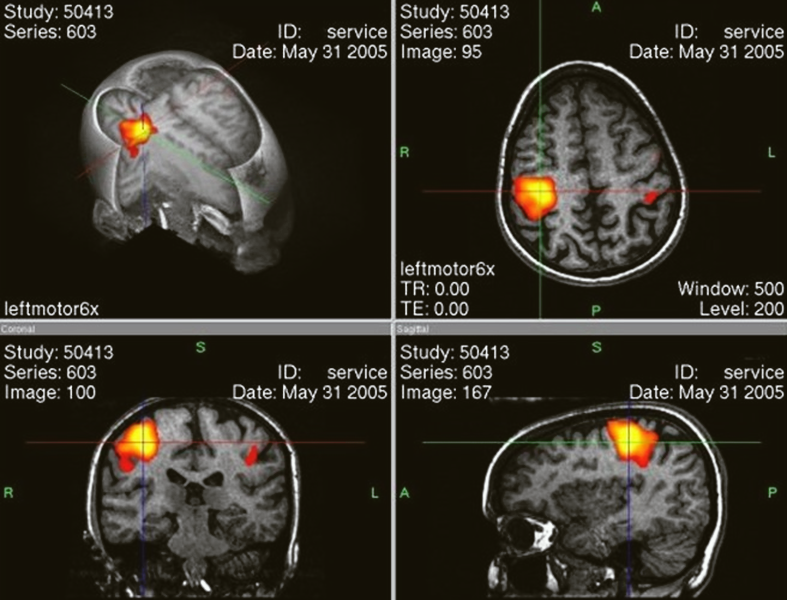

Однако данные нейрофизиологии показывают: в процессе повседневной жизни мы используем практически весь мозг, просто не все его участки активны одновременно. Разные зоны включаются в зависимости от задачи: восприятие, движение, память, речь. Даже во сне мозг не «отключается» — он регулирует дыхание, следит за внутренними процессами, обрабатывает полученную за день информацию.

Разные участки мозга активируются в зависимости от того, чем мы заняты — и это нормально